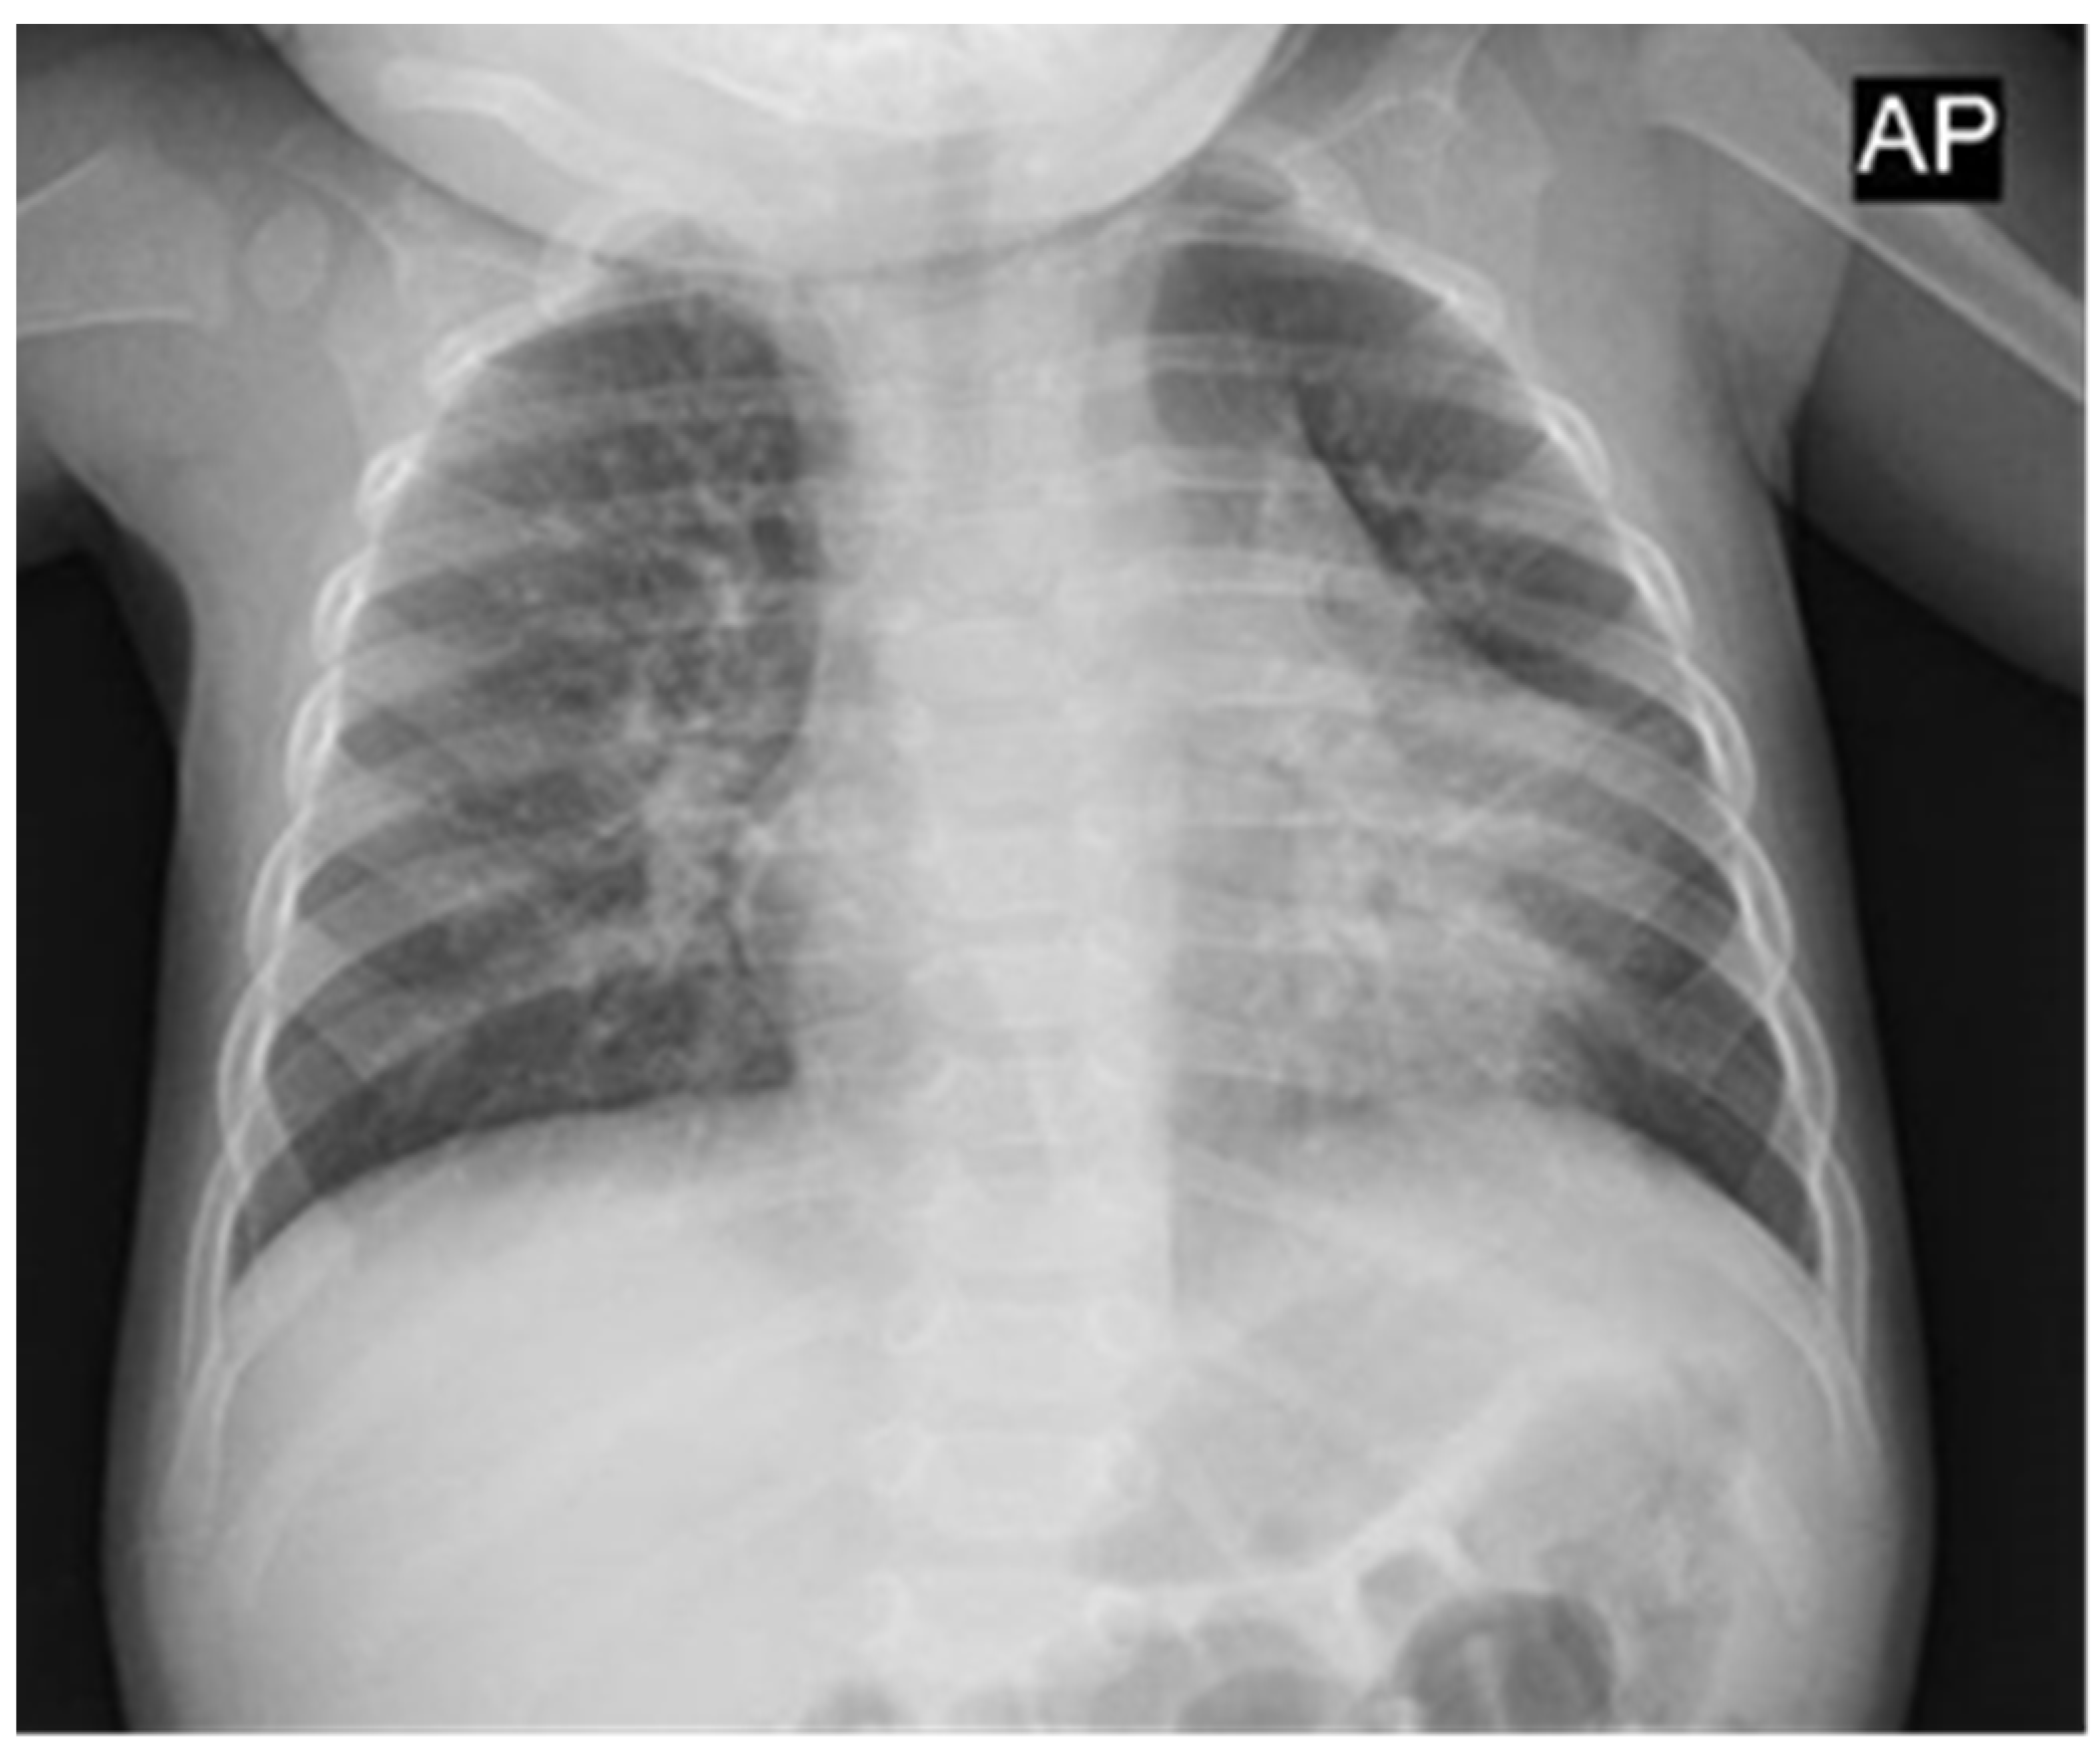

2. Case Report

2.1. Clinical Evolution

2.2. Autopsy Findings